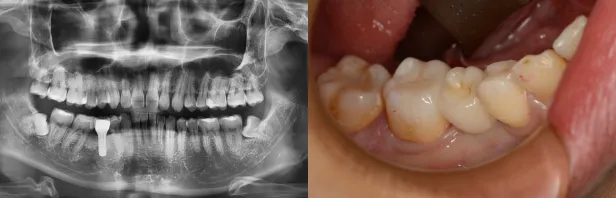

参考症例